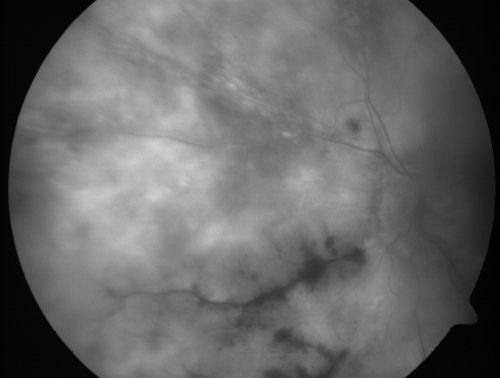

Progressive Outer Retinal Necrosis 77 Year Old Woman with CLL (Acute Retinal Necrosis) (PORN - ARN)

77-year-old woman with CLL who had shingles on the left side of her face about 6 weeks ago then she developed a dendrite in the cornea which was treating about four weeks ago.  She noticed severe vision loss in the left eye just a few days ago and you saw retinitis and she comes in because of that.   Vision OD is 20/25, OS is hand motion